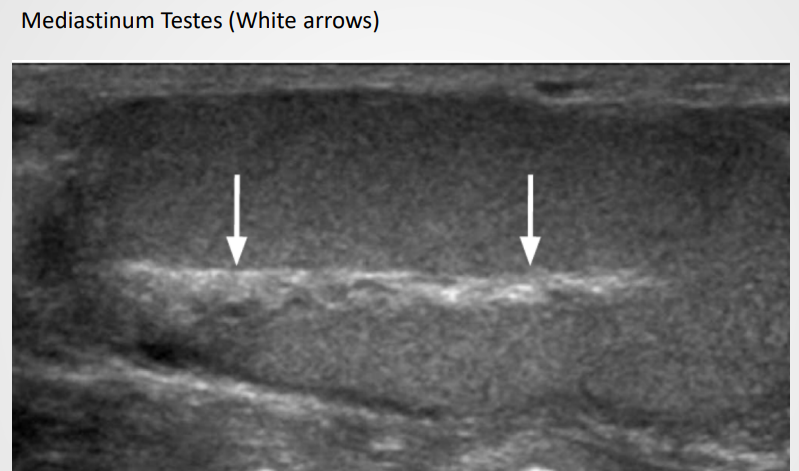

Tunica invaginates to form a linear ehcogenic mediastinum testis

Rete testis may appear as a hypoechoic region near mediastinum and easily visible if dilated